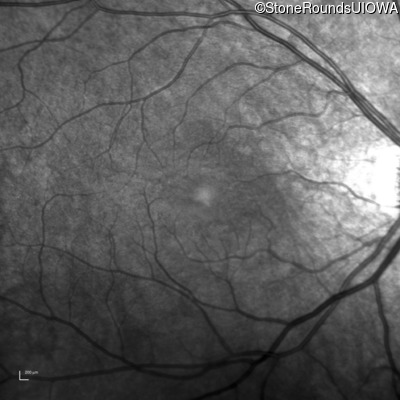

Infrared Fundus Photograph - Left - 20/50

Exemplar